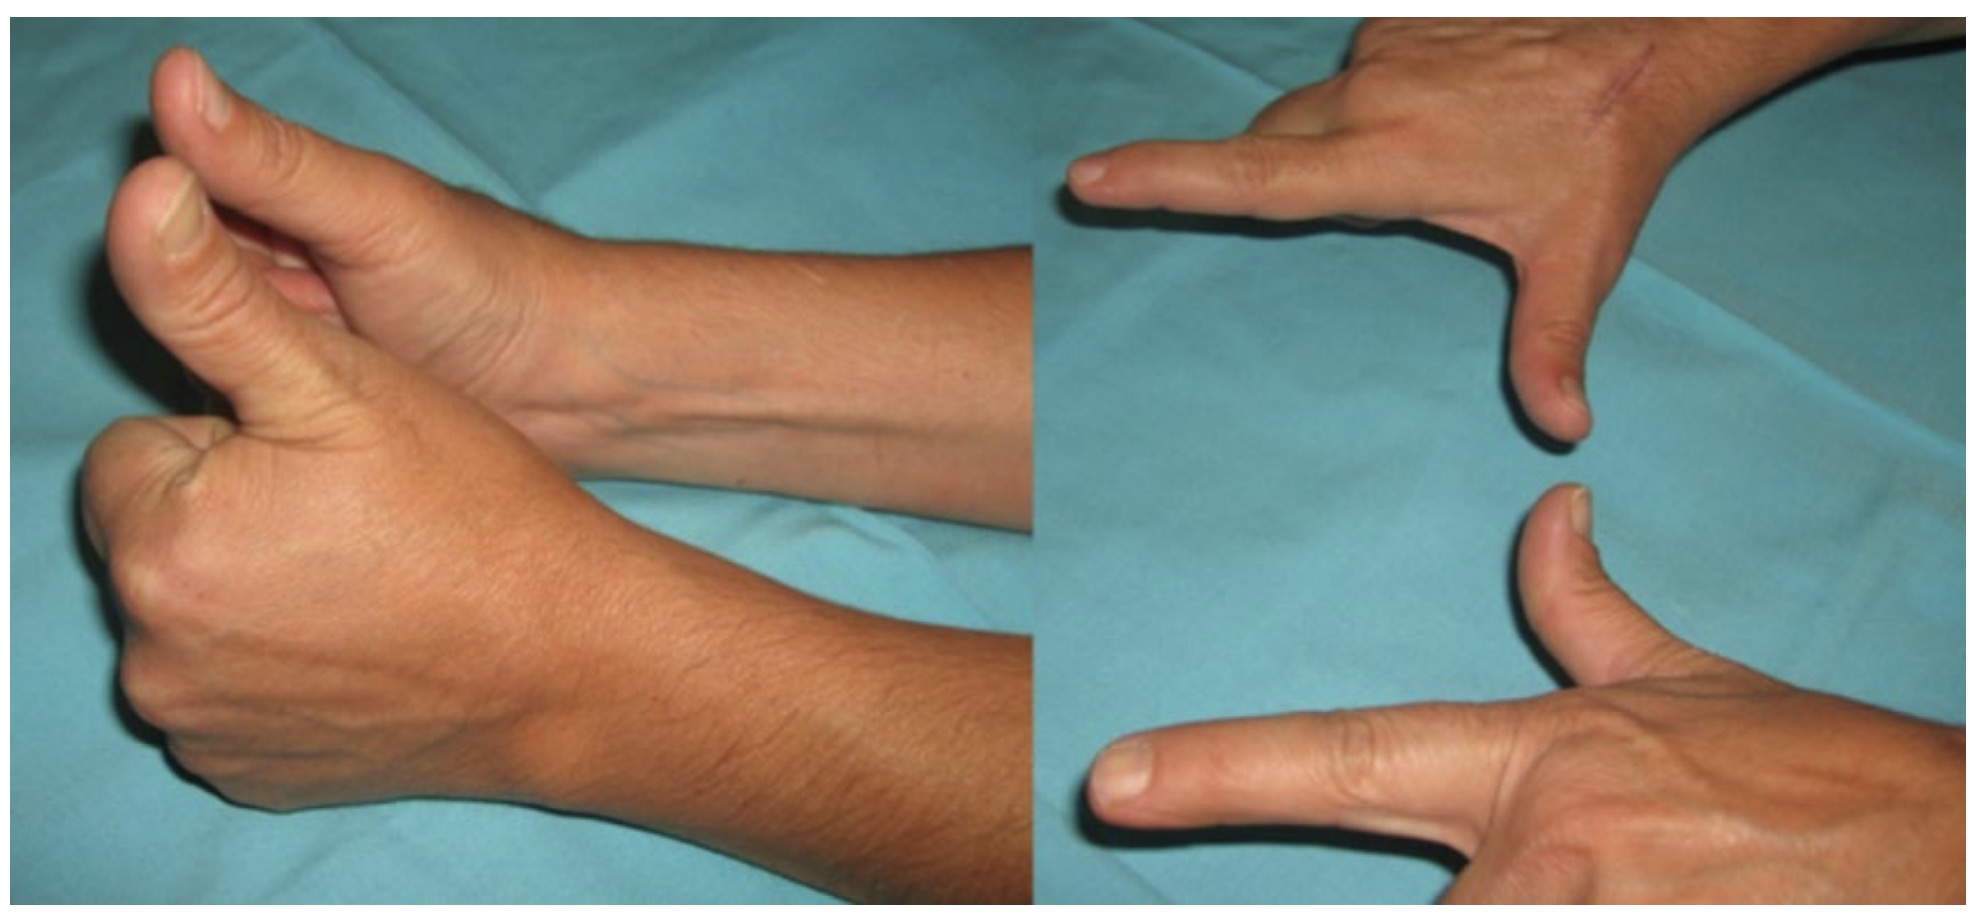

La técnica del lazo para la reparación de lesiones tendinosas, especialmente en la reparación de la rotura del extensor largo del pulgar, ha demostrado eficacia y resultados clínicos satisfactorios. Para esta, se ha desarrollado la técnica del lazo en las transferencias del extensor corto del pulgar o del extensor propio del índice al extensor largo del pulgar deteriorado. La transferencia realizada para reparar el extensor largo del pulgar con la técnica del lazo ha sido eficaz y segura, y se ha conseguido la recuperación de la extensión del pulgar, con lo que se ha reafirmado el valor del nudo con lazo como medio de unión.

La aplicación en la práctica clínica del nudo antes descrito se resume en la capacidad de sustituir la función motora perdida, tras un mecanismo lesional abierto o cerrado del tendón extensor largo del pulgar. El nudo es la herramienta que posibilita que otro tendón asuma la unidad motora funcional del tendón lesionado mediante la tracción de este.

El nudo con el lazo transfixiante es una nueva y original forma para unir elementos. Sus propiedades más significativas son seguridad, eficiencia y fortaleza. Su utilidad en la cirugía está demostrada en los trabajos anteriormente publicados. Futuras aplicaciones en la industria tendrán la oportunidad de evaluarlo con mayor detalle.

La aplicación de la técnica del lazo transfixiante en la reparación tendinosa y, en especial, del tendón extensor largo del pulgar es una aportación muy válida a la cirugía de la mano.